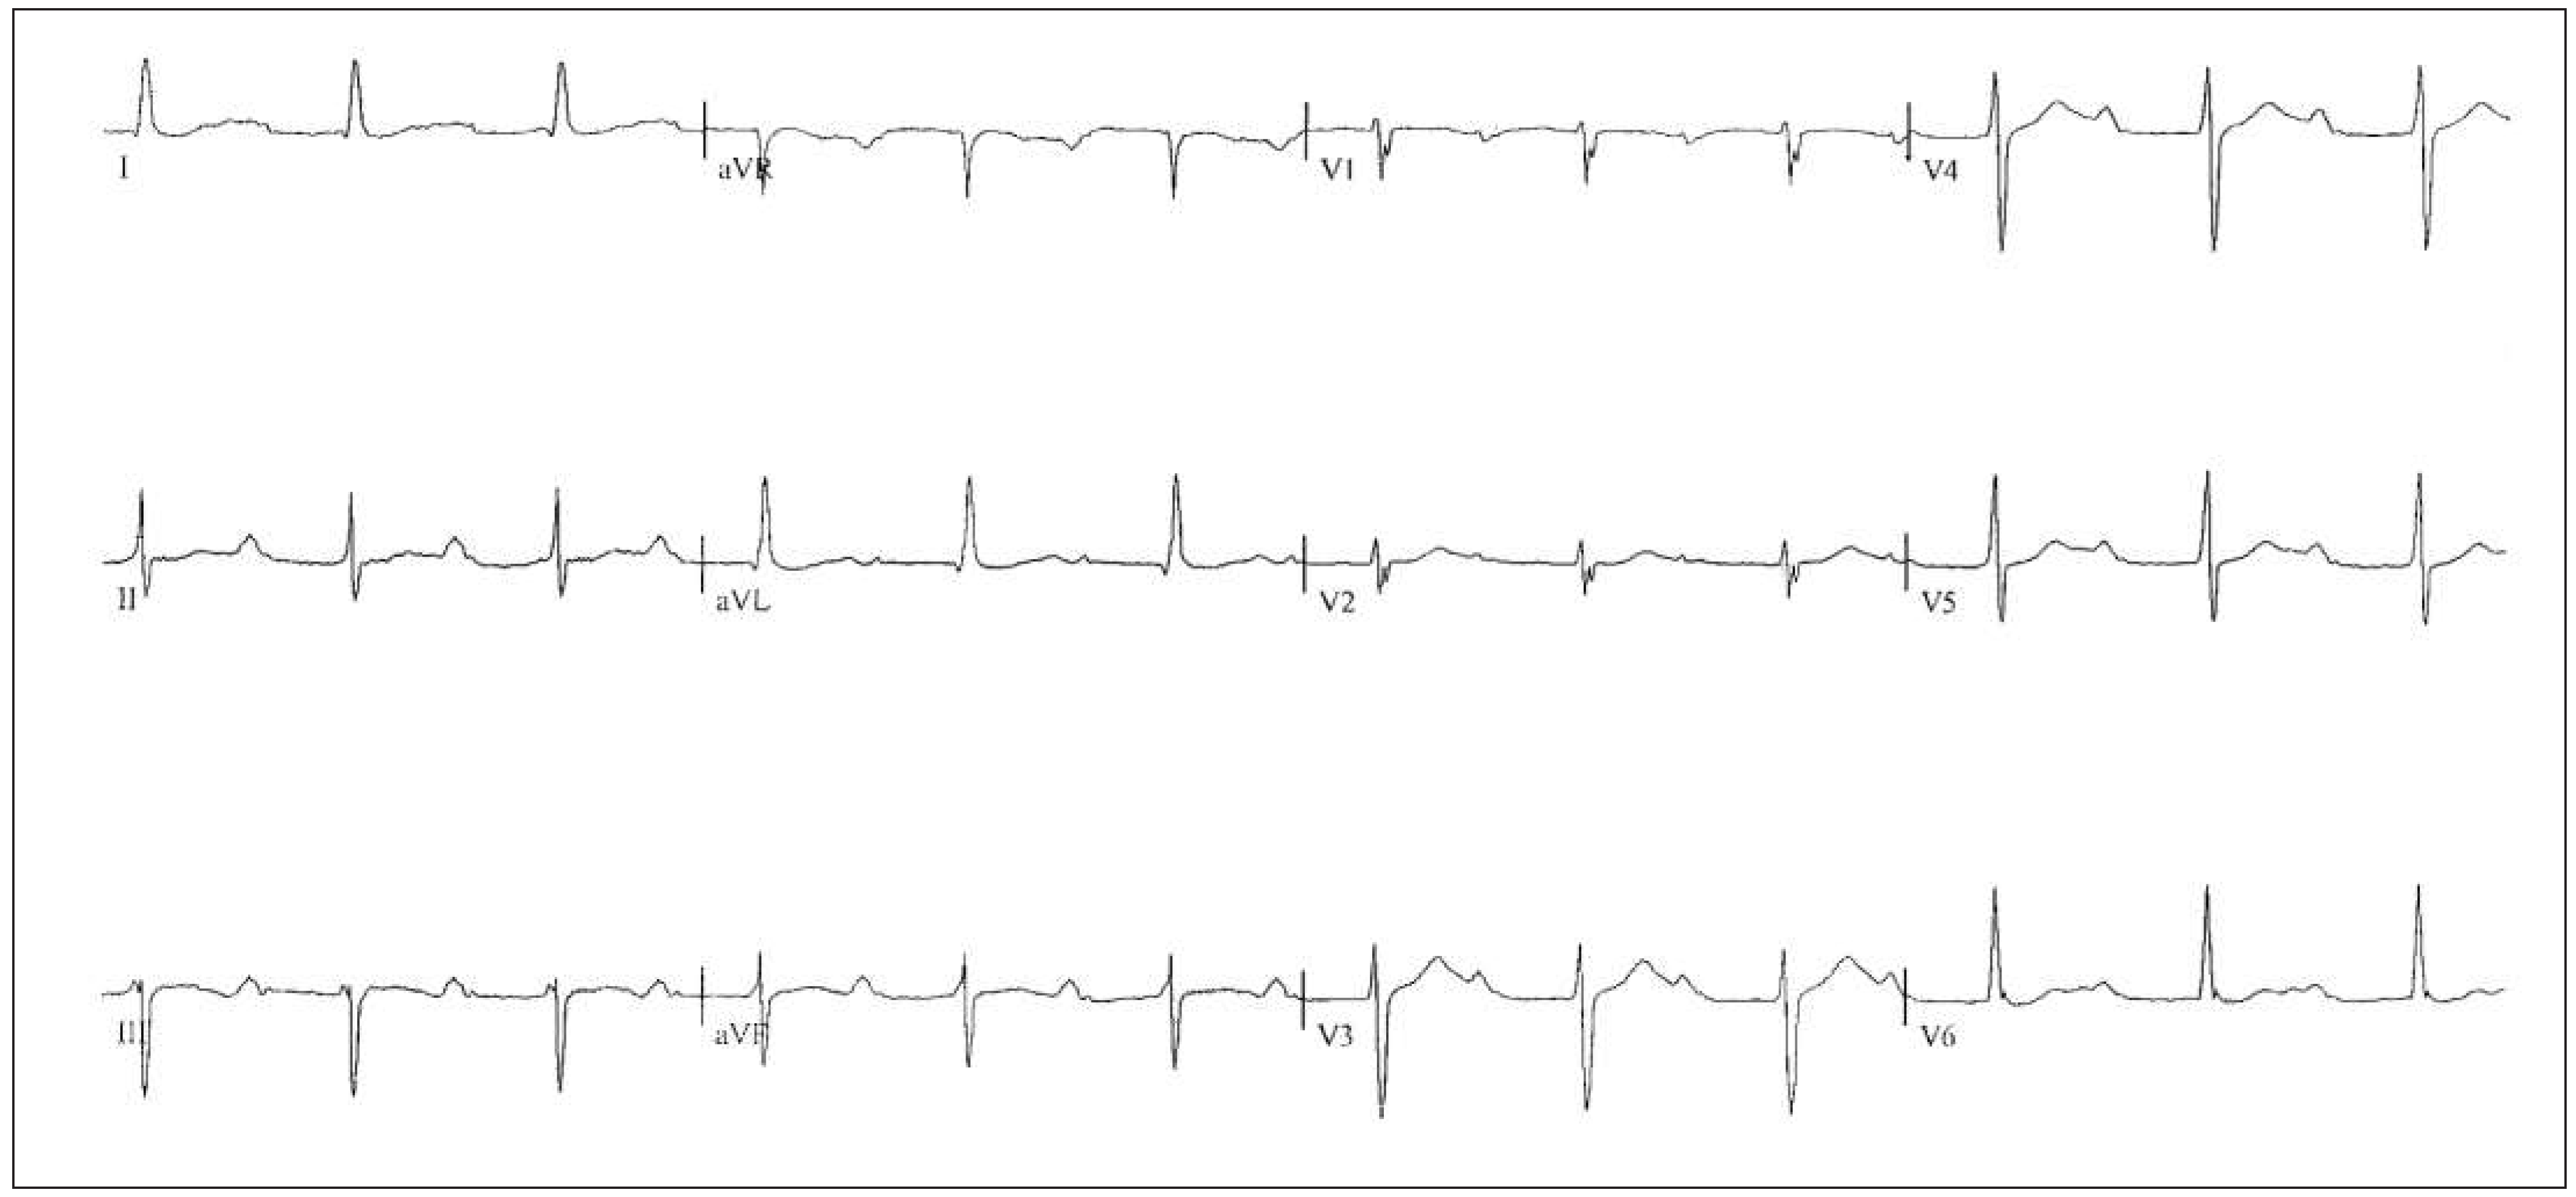

Six-month follow-up

Sixteen-month follow-up